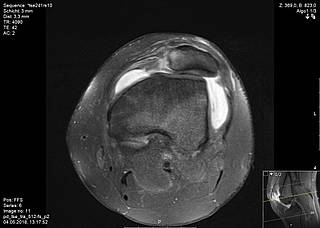

MPFL demolition and trochlear dysplasia

In surgical interventions, the so-called MPFL (medial patellofemoral ligament) is the focus of treatment, because it is the main stabiliser of the patella (kneecap) in flexion degrees close to extension and works against a large part of the outward forces. This ligament is torn in about 90% of cases after a patellar dislocation. During the operation, it is replaced by a tendon from the patient's own body (gracilis or quadriceps tendon), which is tensioned in the course of the MPFL. If there are other factors that promote instability, these are also included in the therapy. For example, it may be necessary to create a new sliding groove in the femur for the kneecap in order to achieve bony stability.